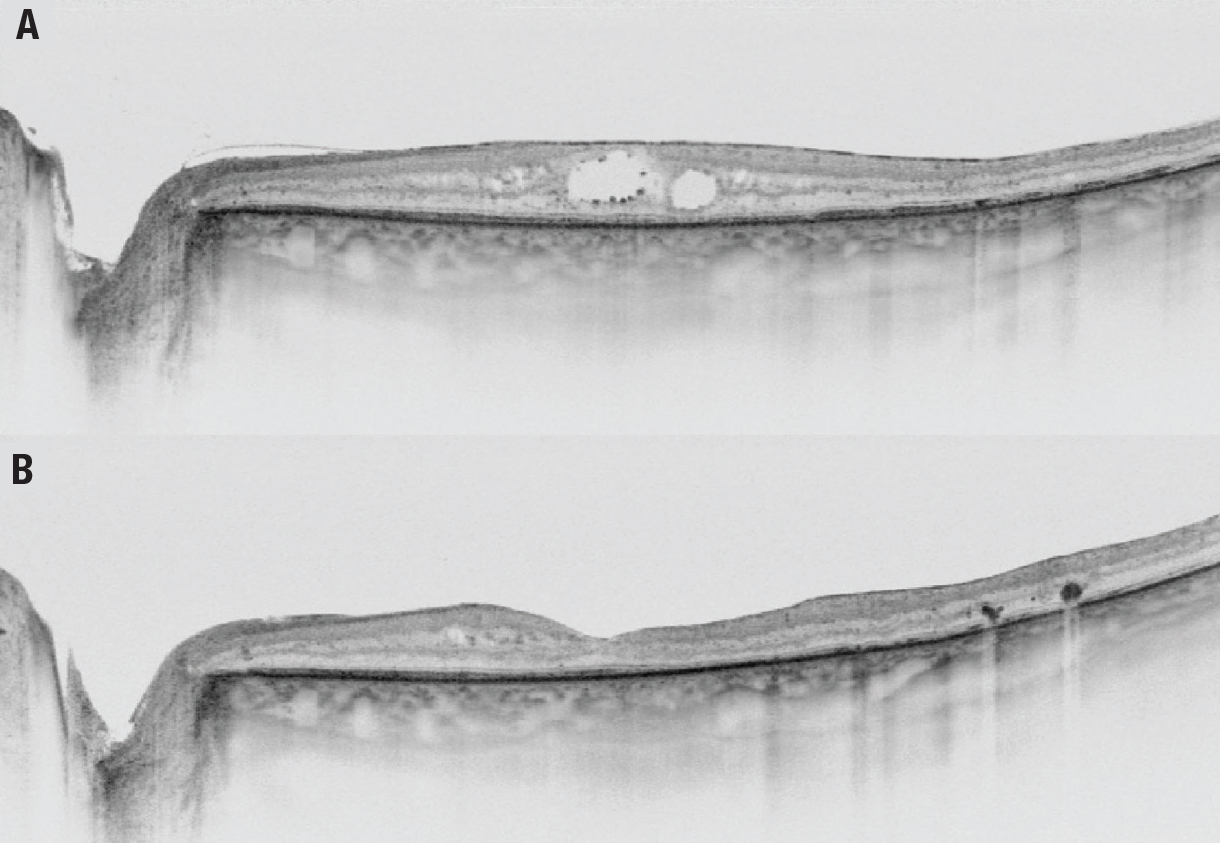

| Figure 2. Swept-source optical coherence tomography of diabetic macular edema in a 66-year-old man A) before surgery and B) one year after surgery. |

Proper patient selection for surgery is paramount (Figure 2). It has been reported that the best results after vitrectomy are obtained in patients with an intact external limiting membrane and ellipsoid zone.8 A study from Japan reported that patients with subretinal fluid in diffuse macular edema also benefit from surgery.9